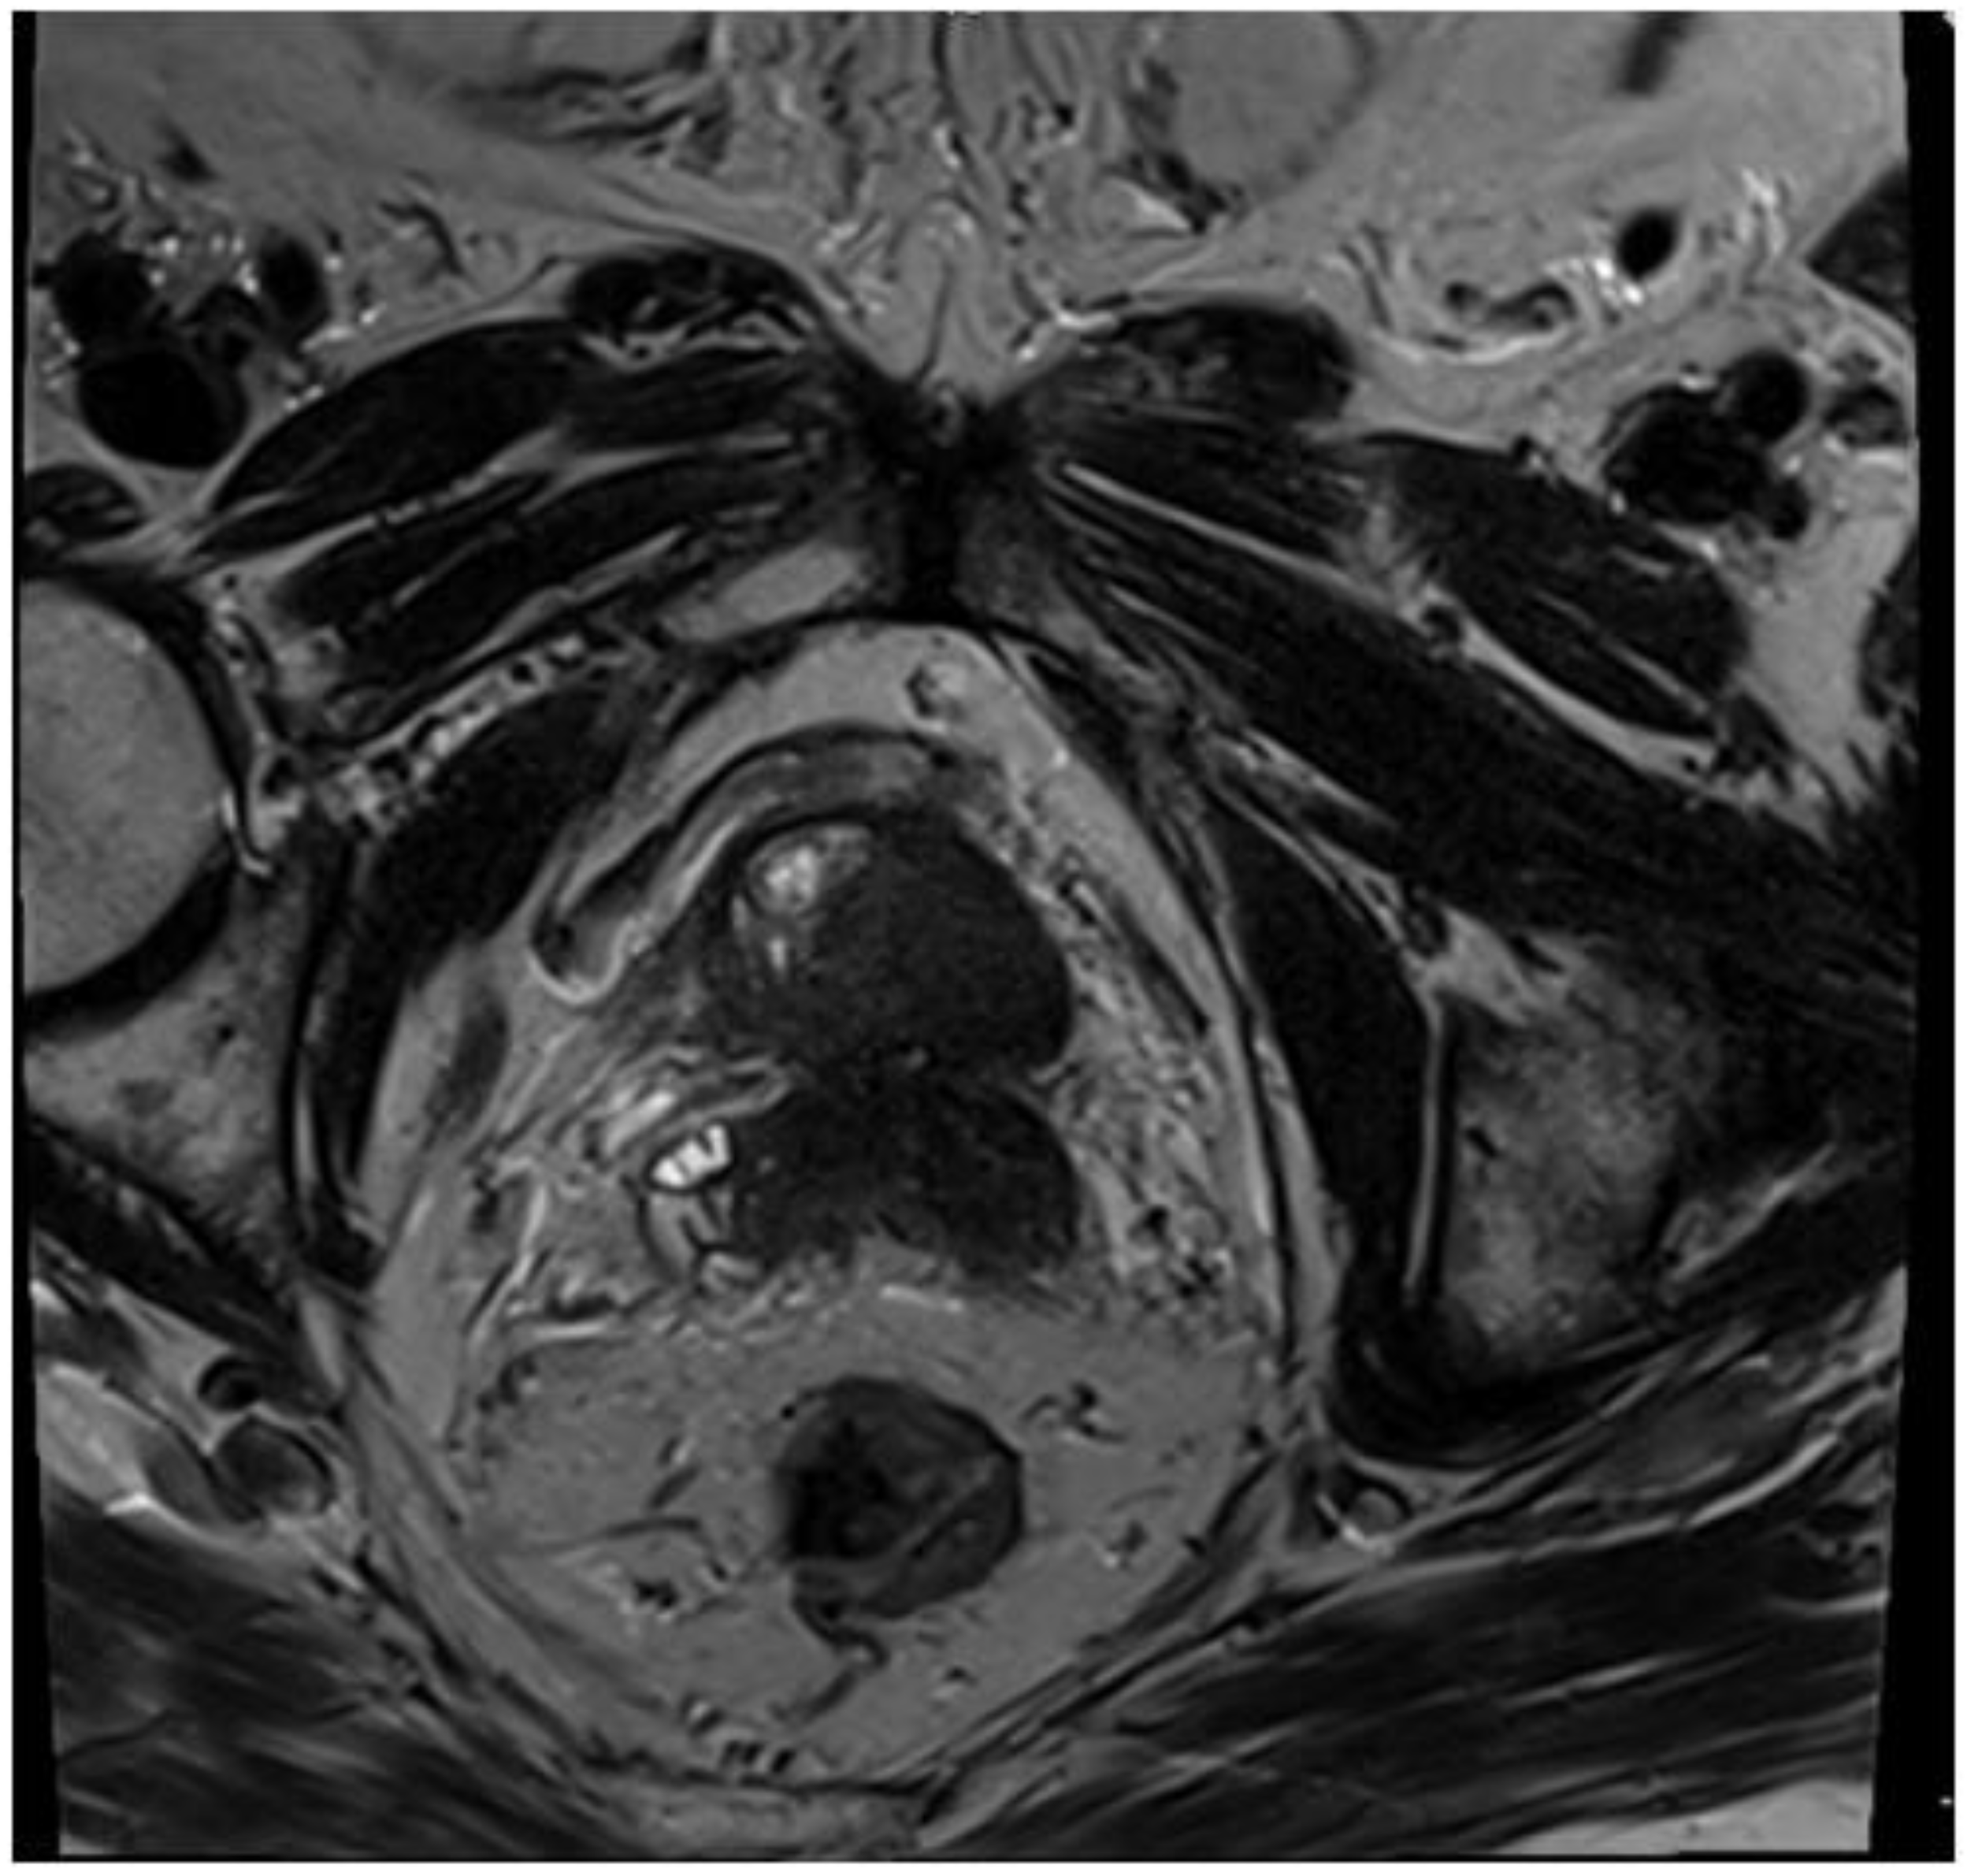

2. Case Presentation